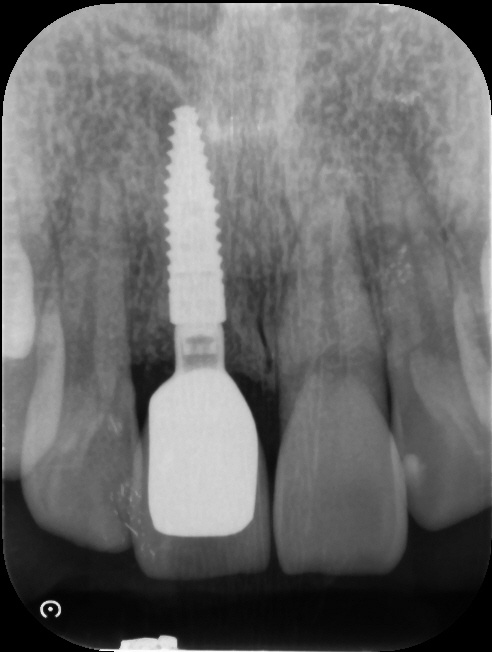

Before

After

治療内容

インプラント1本・骨造成・歯肉移植

治療期間・回数

約4ヶ月・約5回

費用

520,000円

治療のリスク

外科手術が必要になるため、患者様に体力的な負担がかかる。